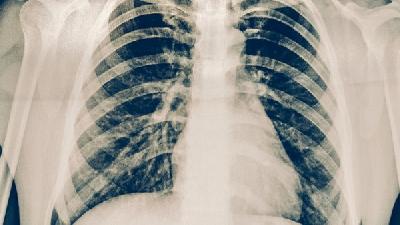

CT顯示肺結(jié)核,但無癥狀

CT顯示肺結(jié)核,但無癥狀,可能是早期病情、隱性肺結(jié)核、卡介苗接種所致。